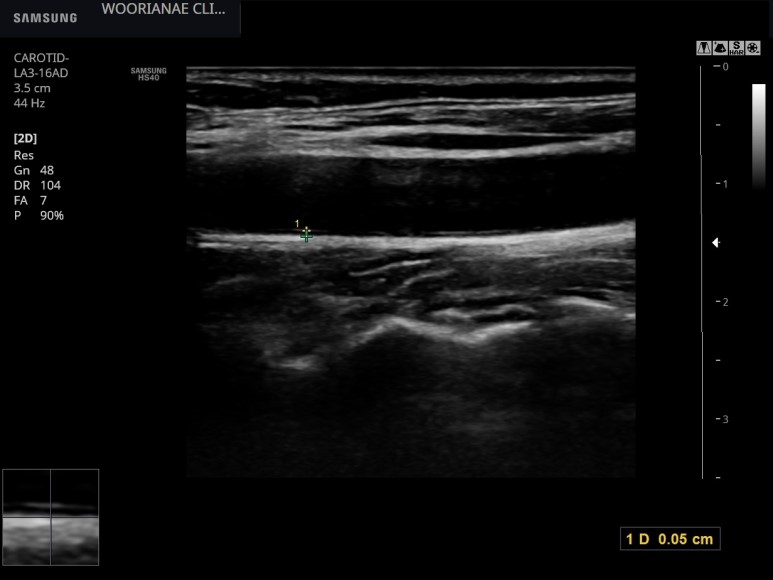

흡연하지 않는 부인의 경동맥 내막 모습